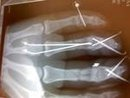

So I have been debating weather to post this or not and have decided I should. On new years eve the snow slid off my roof into my driveway I wAnted to get it cleaned up before it froze in. I was home alone with my two young boys 7 and 2. Was not thrilled about them being inside alone but had to get the snow taken care of . I knew going in if would be hard blowing with the cub cadet 149 with single stage but doable . It clogged several times but I expected so I would disengage drive forward to stop auger back up and clean out the shoot. All was going great and I was almost done but had been a while and boys were in the house alone . I got in a hurry as it was turning dark and it clogged up I disengaged and hopped off to clean it out and bang . Notice I missed a step. So I'm sitting here writing this with three broken fingers which have 7 pins holding them together . So please everyone be careful this winter it only takes a second to make a dumb mistake

This is the X-ray of the fingers just to drive the safety reminder home .

Markcuda pto was disengaged just hadn't stopped spinning yet and it's a 1973 so does not have pto safety off